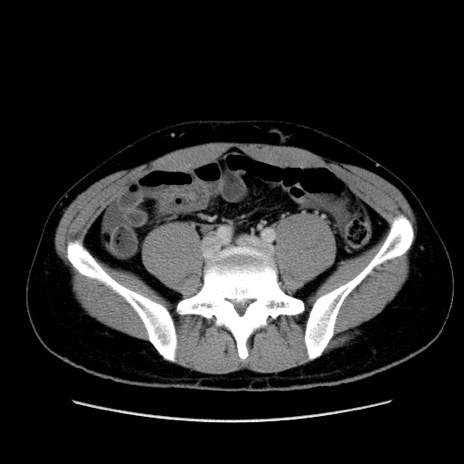

症例36(横断像)

【症例】20歳代 男性

【主訴】心窩部痛

【現病歴】今朝より上腹部痛あり。一旦軽快していたが再度出現したため救急要請。昨日夕に白身の魚を含む刺身を食べた。

【身体所見】BP 136/89mmHg、HR 74/min、BT 37.0℃、腹部:膨満、軟、心窩部に圧痛あり。反跳痛なし、筋性防御なし、腸雑音やや亢進あり。

【データ】WBC 17700、CRP 0.48